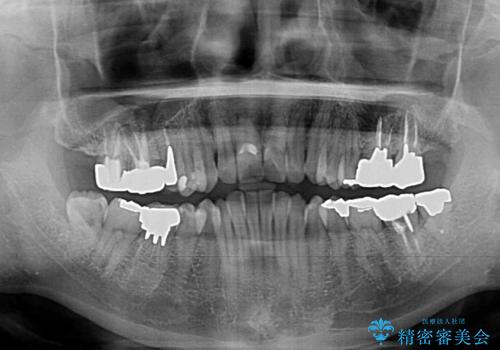

受け口傾向の咬み合わせ 前歯のデコボコをワイヤー矯正で素早く改善

- 前歯の見た目を気にして来院された患者様です。

前歯のクロスバイトは、改善の途中で歯髄壊死を起こすリスクが高くなるため、マウスピース矯正よりもワイヤー矯正をお勧めしております。

この患者様もクロスバイトはあっという間に改善され、1年強で速やかに治療を終えることができました。